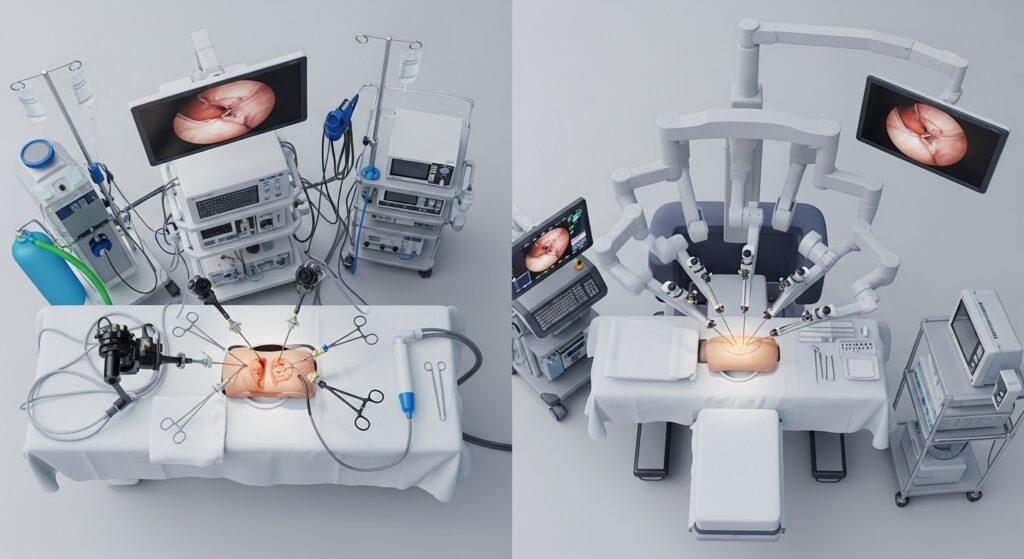

La cirugía robótica se ha convertido en una herramienta clave en la urología moderna gracias a su precisión, menor invasión y recuperación más rápida. Sin embargo, no todas las personas son candidatas para este tipo de intervención. La selección de pacientes para cirugía robótica es un proceso médico detallado que evalúa diferentes factores para garantizar que esta tecnología se use de forma segura y eficaz.

1. Tipo de procedimiento quirúrgico

No todos los procedimientos requieren tecnología robótica. Esta técnica se recomienda principalmente en intervenciones que demandan alta precisión, como cirugías prostáticas, renales complejas o reconstructivas. Tu diagnóstico influye directamente en si esta opción es viable para ti.

4. Experiencia del equipo médico

La cirugía robótica requiere experiencia especializada. Por eso, otro criterio importante es que el hospital cuente con el equipo adecuado y cirujanos capacitados en esta tecnología. La selección adecuada de pacientes también depende de la preparación del personal que llevará a cabo el procedimiento.